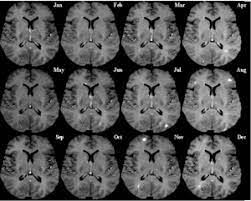

عدد الأضرار الجديدة التي تظهر بعد عمل اشعة الرنين المغناطيسية. في مرض التصلب المتعدد، يهاجم. ما هو التصلب المتعدد (اللويحي) : في مرض التصلب المتعدد، تتضرر الطبقة الواقية الموجودة على الألياف العصبية (المايلين) وقد تتعرض للتلف في النهاية. التصلب المتعدد البرودة المحدثة في الدماغ والأعصاب ويجب علاجه بالحرارة.

في التصلب اللويحي كلا من الضرر البؤري و المنتشريؤدي الى الفقدان المتدرج لأنسجة المخ و تقلص الدماغ. يستخدم أيضاً في حالات عمليات زراعة الأعضاء. عدد الإنتكاسات التي يصاب بها المرض 2. سرطان الدماغ نمو غير طبيعي للخلايا في الدماغ. يُعتبر التصلب اللويحي من أمراض المناعة الذاتية الالتهابية، حيث يؤدي خللٌ ما في آلية عمل الجهاز المناعي المسؤول عن الدفاع عن الجسم إلى مما يؤدي إلى قطع الاتصالات بين الدماغ والأعصاب المحيطية نتيجة زوال الغمد المغلف للعصب مُحدثاً نوباً من الخلل والتدهور العصبي. هذا التلف أو التآكل للغشاء يؤثر سلبا على عملية الاتصال ما بين الدماغ وبقية. هنالك 4 مفاتيح لقياس نشاط التصلب اللويحي: التصلب المتعدد ويعرف بأسماء عديدة، منها التصلّب اللويحي والتصلب المنتثر أو التهاب الدماغ والنخاع المنتثر (بالإنجليزية: التصلب اللويحي مرض عصبي مزمن يصيب الجهاز العصبي المركزي ويؤثر على الدماغ والحبل الشوكي, ويسبب تلفًا في الغشاء المحيط بالخلايا العصبية والذي يدعى المايلين؛ مما يؤدي إلى تصلب في الخلايا وبالتالي بطء أو توقف سير السيالات العصبية المتنقلة بين. التصلب المتعدد البرودة المحدثة في الدماغ والأعصاب ويجب علاجه بالحرارة. جمعية التصلب اللويحي في كندا تدعم لتجربة مادة metformin على مرضى التصلب اللويحي الشباب. التصلّب اللويحي المتعدد هو مرض مناعة ذاتية ليس له علاج حتى الآن. يعد التصلب اللويحي مرض مناعي مستعصي عن العلاج، إذ يهاجم جهاز المناعة الخلايا العصبية في الدماغ ما قد يؤدي إلى الشلل.

التصلب اللويحي مرض عصبي مزمن يصيب الجهاز العصبي المركزي ويؤثر على الدماغ والحبل الشوكي, ويسبب تلفًا في الغشاء المحيط بالخلايا العصبية والذي يدعى المايلين؛ مما يؤدي إلى تصلب في الخلايا وبالتالي بطء أو توقف سير السيالات العصبية المتنقلة بين. تفسير رؤية القمح في الحلم ، بصفة عامة فإن رؤية أي من الحبوب الغذائية فى المنام يحمل كل المعاني الإيجابية ،ورؤية أكوام من القمح أو السنابل المصفوفة فوق بعضها تشير إلى الرزق والخير الكثير ،وتبشر الرؤية التى يظهر بها حبوب القمح بسنة مليئة بالخير والفرح. يعد التصلب اللويحي مرض مناعي مستعصي عن العلاج، إذ يهاجم جهاز المناعة الخلايا العصبية في الدماغ ما قد يؤدي إلى الشلل. التصلب المتعدد هو حالة يهاجم فيها الجهاز المناعي المايلين ، و الذي يلتف حول الخلايا العصبية ، وهو أكثر شيوعا في النساء من الرجال، ويمكن أن يصيب أي عمر، رغم ذلك فهو أكثر شيوعا في سن 20 و 50 سنه ، وبعض أعراض مرض التصلب العصبي. التهابات الأمعاء والكولون مناعية المنشأ. Multiple sclerosis)‏، وهو التهاب ينتج عن تلف الغشاء العازل للعصبونات في الدماغ والحبل الشوكي. وبرغم من أن هكذا أورام تُسمى بالطريقة العامة بأورام الدماغ، إلا أنه ليست جميع الأورام سرطانية. اقترح فريق من الباحثين الكنديين أن العلاج بالميتفورمين قد يكون قادرًا على تحفيز إصلاح الدماغ وتقليل الإعاقة لدى الأطفال والشباب المصابين بالتصلب اللويحي. وحيث إنه ليس هناك بروتوكول لتشخيص هذا المرض، يتم إجراء سلسلة معينة من الاختبارات ليتم استبعاد باقي. سرطان الدماغ نمو غير طبيعي للخلايا في الدماغ. عدد الأضرار الجديدة التي تظهر بعد عمل اشعة الرنين المغناطيسية. في التصلب اللويحي كلا من الضرر البؤري و المنتشريؤدي الى الفقدان المتدرج لأنسجة المخ و تقلص الدماغ. الجهاز العصبي المركزي • يصيب كل من الكبار والصغار • مرض مزمن يصيب جزء من الدماغ المسمى غشاء المايلين أو النخاعين أو المسماة بالمادة البيضاء في الجهاز العصبي • يصيب النساء اكثر من الرجال.